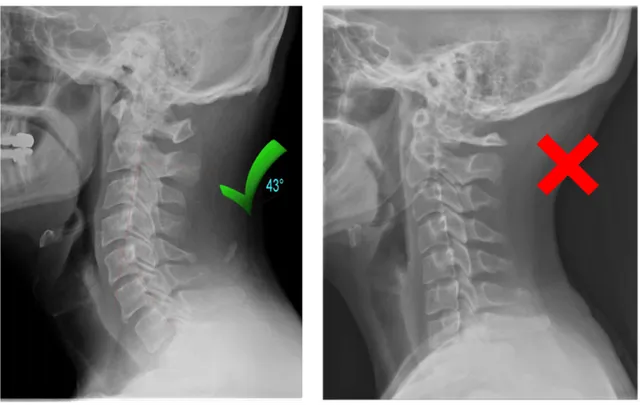

2. Your Neck Has Lost Its Natural Curve

Years of looking down at phones, working at desks, and poor sleeping posture can flatten the natural curve of your neck.

This leads to collapsed vertebrae, pinched nerves, and chronic pain that no massage or pillow can fix.

✓ Restoring the natural curve in your neck